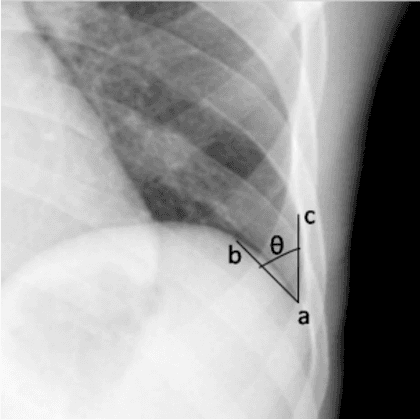

Abstract:We propose a BlackBox \emph{Counterfactual Explainer} that is explicitly developed for medical imaging applications. Classical approaches (e.g. saliency maps) assessing feature importance do not explain \emph{how} and \emph{why} variations in a particular anatomical region is relevant to the outcome, which is crucial for transparent decision making in healthcare application. Our framework explains the outcome by gradually \emph{exaggerating} the semantic effect of the given outcome label. Given a query input to a classifier, Generative Adversarial Networks produce a progressive set of perturbations to the query image that gradually changes the posterior probability from its original class to its negation. We design the loss function to ensure that essential and potentially relevant details, such as support devices, are preserved in the counterfactually generated images. We provide an extensive evaluation of different classification tasks on the chest X-Ray images. Our experiments show that a counterfactually generated visual explanation is consistent with the disease's clinical relevant measurements, both quantitatively and qualitatively.